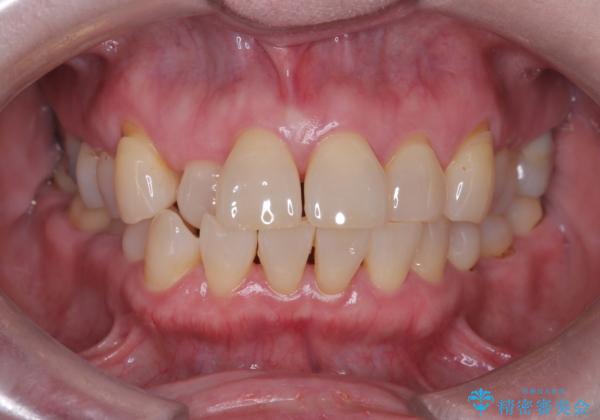

前歯の隙間とへこみが舌で触ると気になる|矯正治療は絶対にしたくない|抜歯即時インプラント+オールセラミッククラウンで審美修復

そのため今回は、右上2番を抜歯し、右上1番および左上1番をオールセラミッククラウンで審美的に修復しました。

矯正によって歯並びや咬み合わせを整えた後、必要に応じて歯の形や色を整えるためにホワイトニングやセラミック治療を行うことで、より自然で美しい仕上がりが期待できます。